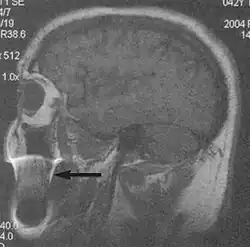

A motion artifact is one of the most common artifacts in MR imaging.[2] Motion can cause either ghost images or diffuse image noise in the phase-encoding direction. The reason for mainly affecting data sampling in the phase-encoding direction is the significant difference in the time of acquisition in the frequency- and phase-encoding directions.[1] Frequency-encoding sampling in all the rows of the matrix (128, 256 or 512) takes place during a single echo (milliseconds). Phase-encoded sampling takes several seconds, or even minutes, owing to the collection of all the k-space lines to enable Fourier analysis. Major physiological movements are of millisecond to seconds duration and thus too slow to affect frequency-encoded sampling, but they have a pronounced effect in the phase-encoding direction. Periodic movements such as cardiac movement and blood vessel or CSF pulsation cause ghost images, while non-periodic movement causes diffuse image noise (Fig. 1). Ghost image intensity increases with amplitude of movement and the signal intensity from the moving tissue. Several methods can be used to reduce motion artifacts, including patient immobilisation, cardiac and respiratory gating, signal suppression of the tissue causing the artifact, choosing the shorter dimension of the matrix as the phase-encoding direction, view-ordering or phase-reordering methods and swapping phase and frequency-encoding directions to move the artifact out of the field of interest.[1]

Flow can manifest as either an altered intravascular signal (flow enhancement or flow-related signal loss), or as flow-related artifacts (ghost images or spatial misregistration). Flow enhancement, also known as inflow effect, is caused by fully magnetised protons entering the imaged slice while the stationary protons have not fully regained their magnetization.[1] The fully magnetized protons yield a high signal in comparison with the rest of the surroundings. High velocity flow causes the protons entering the image to be removed from it by the time the 180-degree pulse is administered. The effect is that these protons do not contribute to the echo and are registered as a signal void or flow-related signal loss (Fig. 2).[1] Spatial misregistration manifests as displacement of an intravascular signal owing to position encoding of a voxel in the phase direction preceding frequency encoding by time TE/2.The intensity of the artifact is dependent on the signal intensity from the vessel, and is less apparent with increased TE.[1]